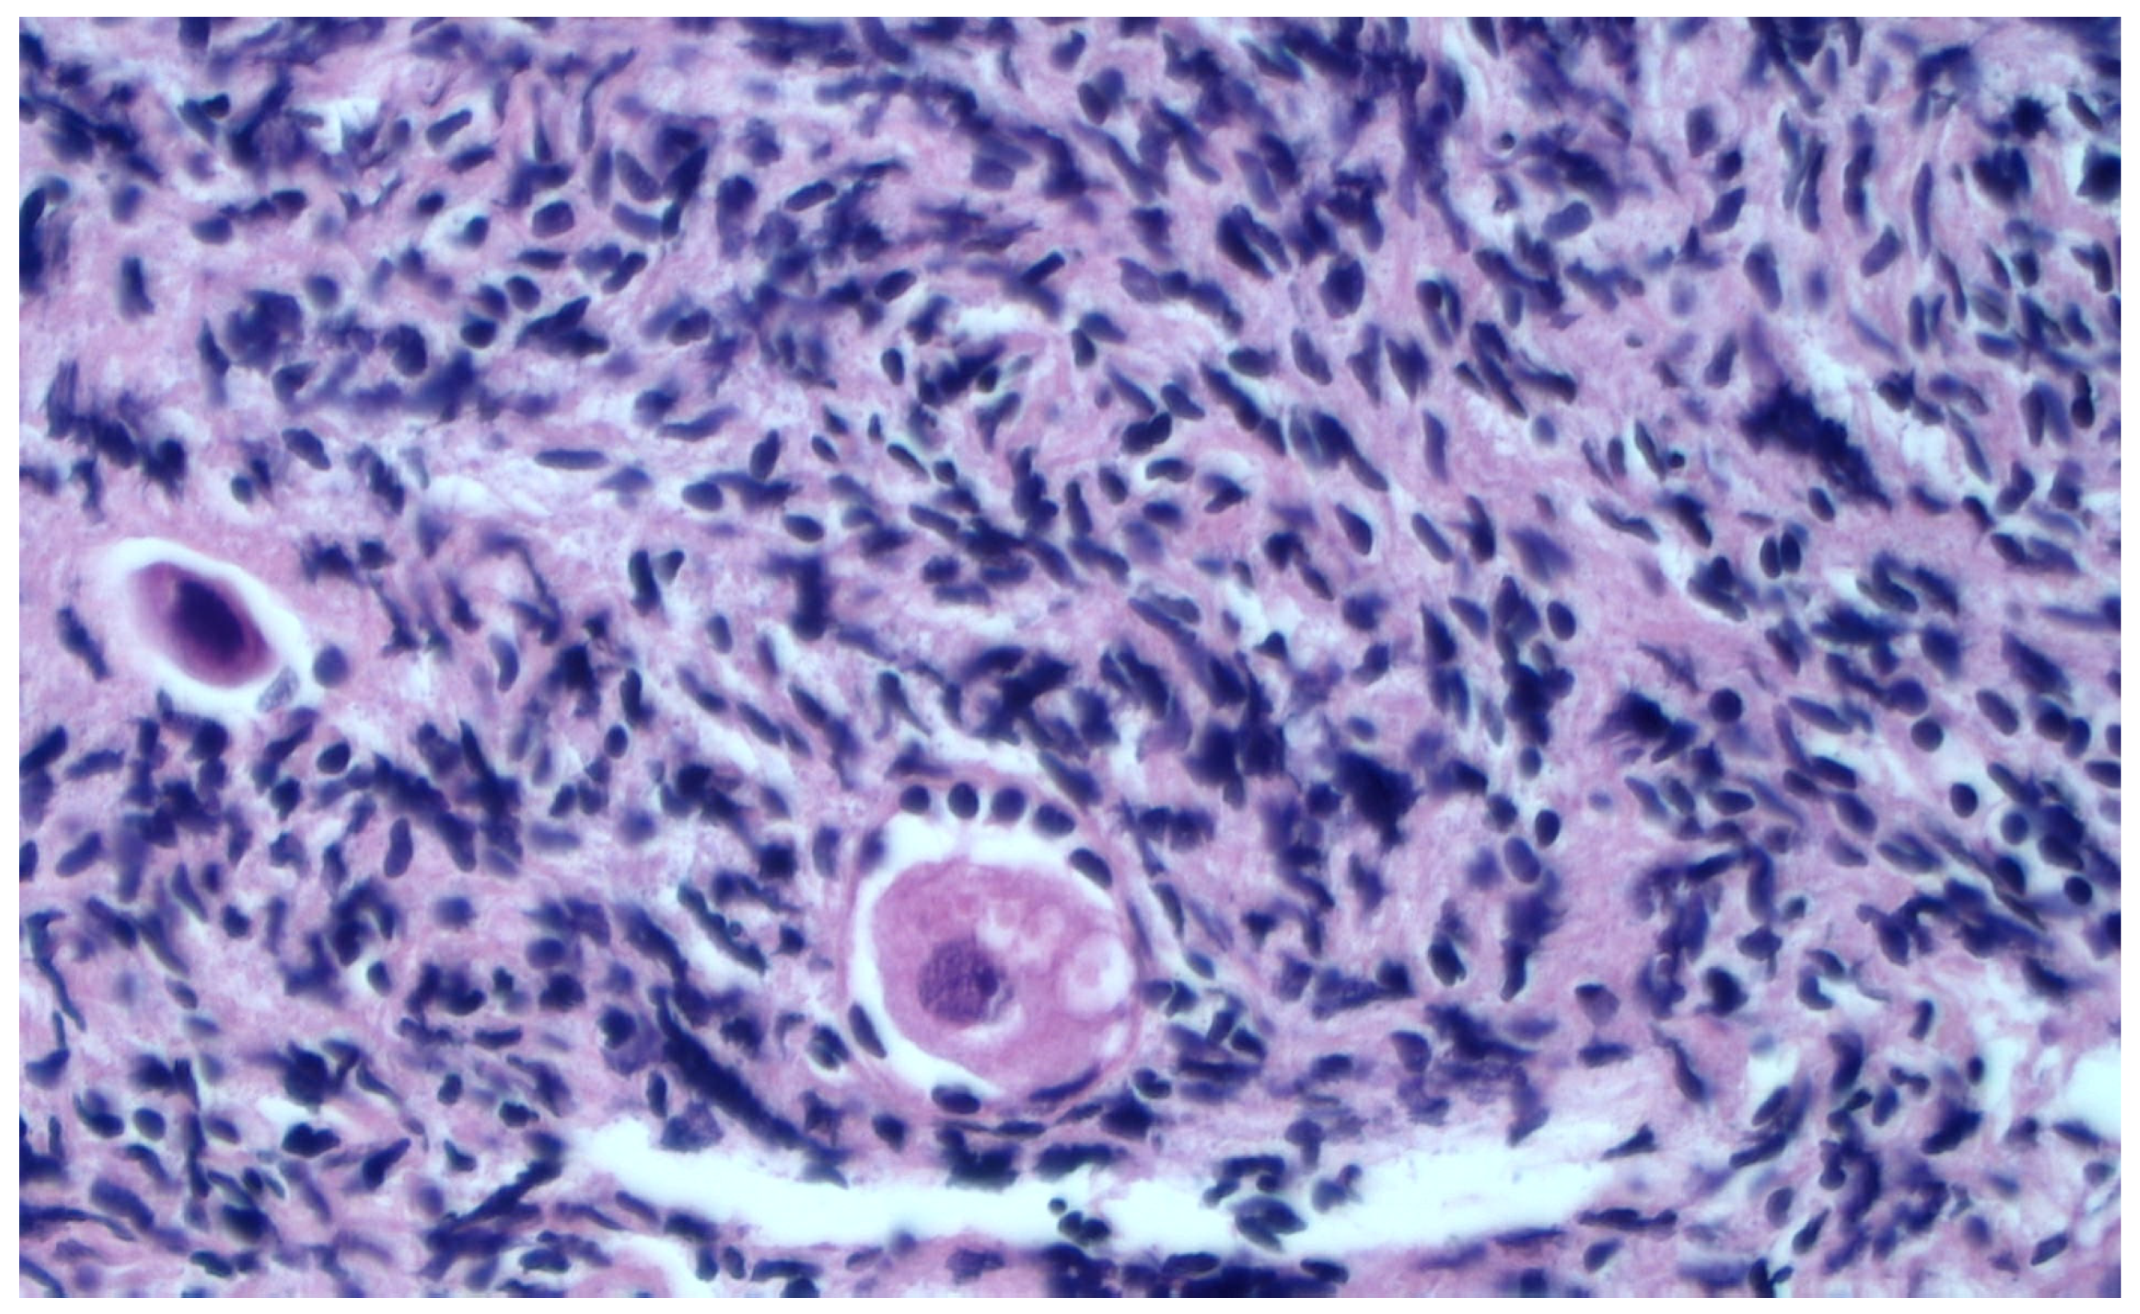

2.5. Histological Evaluation

Histological Evaluation of Thawed Strips